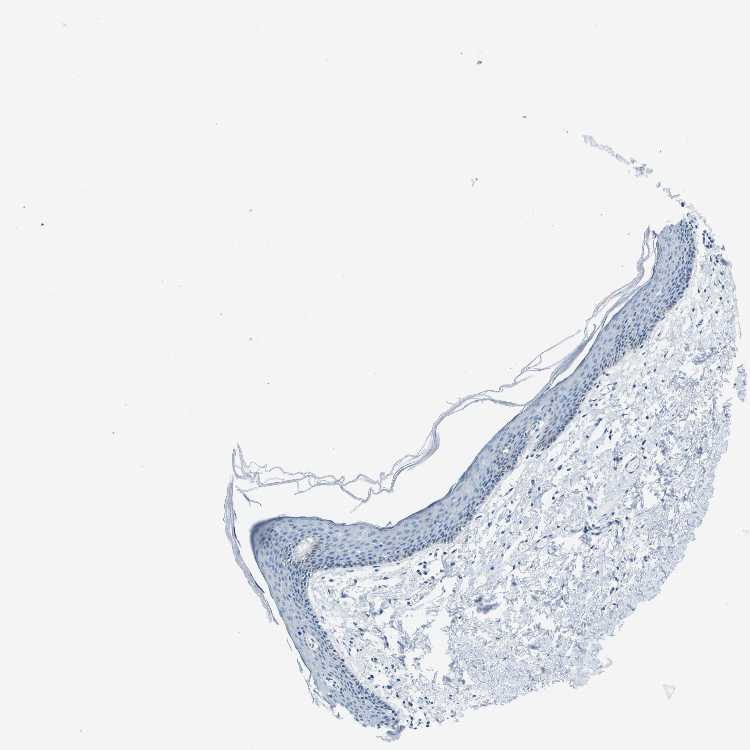

TISSUE PRIMARY DATA SKIN Show tissue menu

Skin

SKIN - Expression summary

SKIN 1 - Antibody stainingi

Antibody staining in the annotated cell types in the current human tissue is reported as not detected, low, medium, or high, based on conventional immunohistochemistry profiling in selected tissues. This score is based on the combination of the staining intensity and fraction of stained cells.

Each image is clickable and will lead to virtual microscopy that enables deeper exploration of all samples and also displays staining intensity scores, fraction scores and subcellular localization as well as patient and tissue information for each sample.

Antibody HPA039291Antibody HPA044062Antibody CAB017448

Langerhans LowNot detectedNot detected

Fibroblasts Not detectedNot detectedNot detected

Keratinocytes LowNot detectedNot detected

Melanocytes Not detectedNot detectedNot detected

SKIN 2 - Antibody stainingi

Epidermal cells MediumLowNot detected